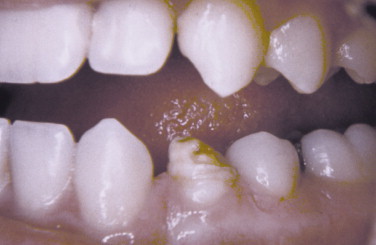

What is this kind of hyperdontia called?

Mesiodens